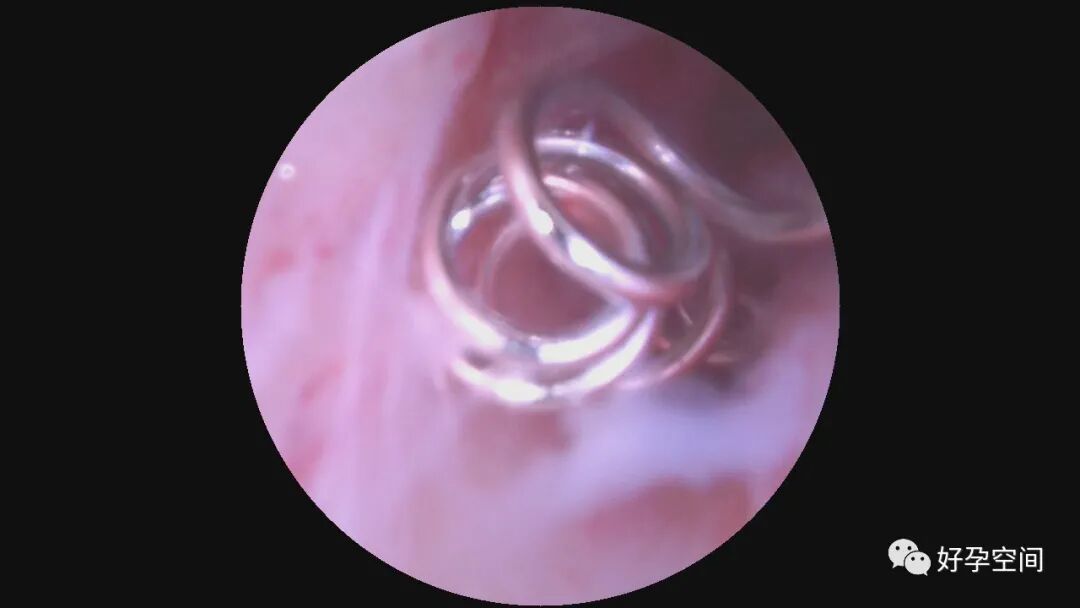

病例1:61岁,G2P1,剖宫产1次,原发性高血压。安环28年,绝经3年。病人肥胖,身高156cm,体重85kg。阴道深,一次性扩阴器勉强暴露宫颈,宫颈萎缩,宫颈钳很难夹持住,反复松脱,置入一次性宫腔镜见节育环坎顿,异物钳艰难取出节育环,偶然见宫腔下段后壁息肉,约1.5cm*1.0cm*0.8cm,异物钳从根部摘除息肉。